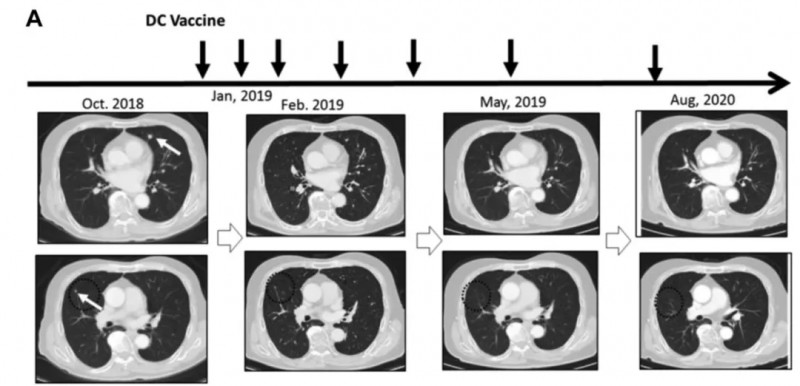

病例6(74岁男性肾癌肺转移患者)

该患者于2018年7月术后2个月出现多发肺转移,因肺静脉血栓无法使用靶向药,2019年1月起接受新抗原肽脉冲DC疫苗治疗。

结果显示:接种3剂后获得部分缓解(PR)。接种完六剂疫苗后,几乎获得完全缓解(CR),肿瘤完全消失。2020年8月复查CT,证实该患者获得了持久完全缓解(CR)(详见下图)。

▲图源“Anticancer research”,版权归原作者所有,如无意中侵犯了知识产权,请联系我们删除